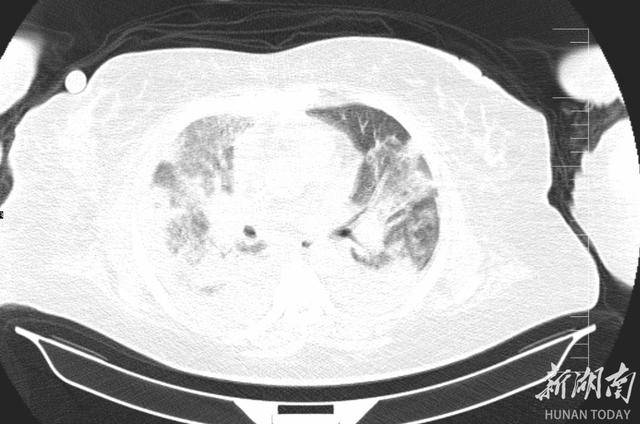

2025 年 12 月 24 日,李阿姨被紧急送入郴州市宜章县人民医院 ICU,她高烧不退、呼吸困难,CT片子上双肺几乎全白了 —— 这是重症肺炎最凶险的信号之一。更麻烦的是,她本身还有肝硬化腹水、十二指肠溃疡大出血等一堆老毛病,所有问题撞在一起,性命危在旦夕。面对如此凶险的病情,救治刻不容缓,ICU 团队火速完成检查并召集多学科会诊,病因被精准锁定:鹦鹉热衣原体感染。

肺部CT可见,重症肺炎较之前大部分被吸收